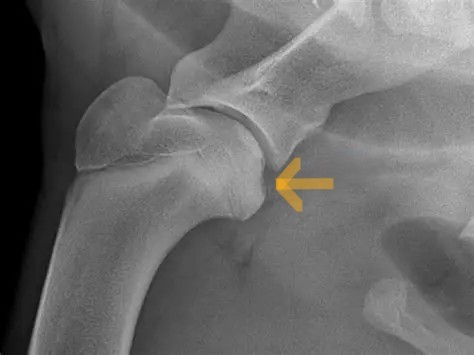

OCD of the Humeral Head

Diagnosis:

The disease is suspected when pain is elicited on flexion of the shoulder with physical examination. An x-ray of the shoulder is usually enough to confirm the diagnosis. In some cases, a CT scan may be recommended to identify small lesions not clearly visible on x-rays.